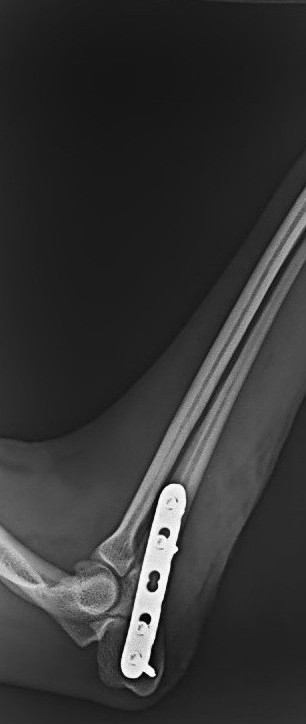

- 骨折(プレート固定等)

・橈尺骨(前肢)骨折整復術 40万円前後